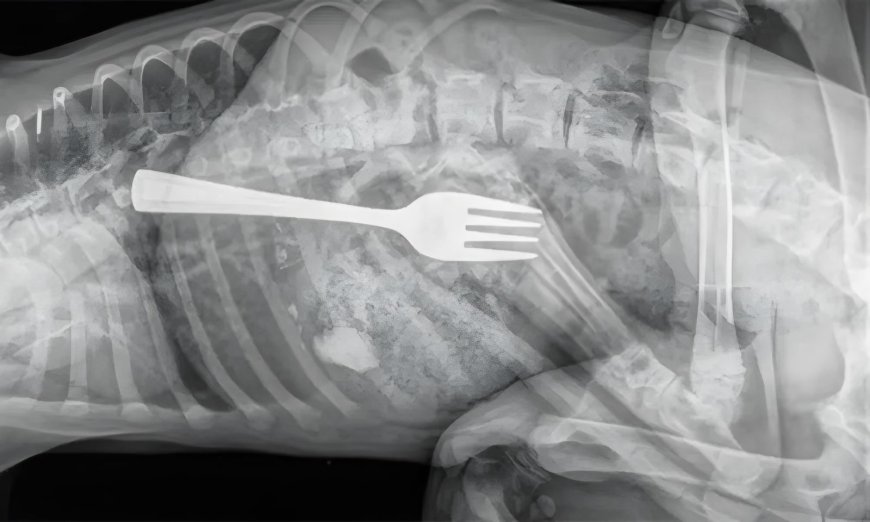

Uma mulher chamou a atenção dos médicos e familiares ao ser hospitalizada após engolir um garfo inteiro durante uma refeição. O caso inusitado ocorreu na última sexta-feira (26), em Guanambi, sudoeste da Bahia.A mulher, que não teve sua identidade revelada, foi encaminhada ao Hospital Geral do município, onde passou por exames de imagem que mostraram o objeto metálico alojado no esôfago, em posição de risco.

Devido a gravidade, a paciente foi transferida para Vitória da Conquista, onde especialistas retiraram o garfo.